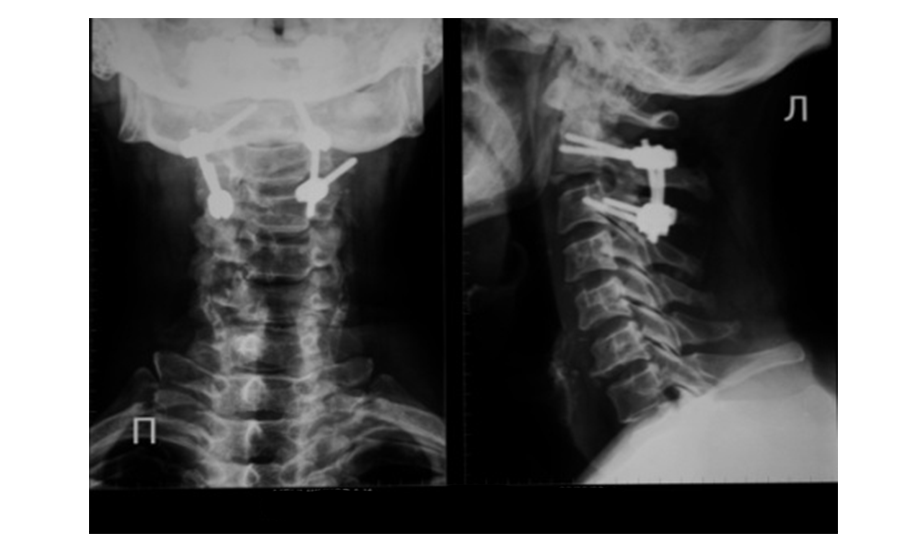

Рис.1 Перелом палача. Тело С2 смещено кпереди относительно С3 (спондилолистез). Стрелкой указан перелом ножки

Рис.2 Произведена репозиция и фиксация перелома палача. Смещение устранено. Ножки позвонка соединены транспедикулярными винтами